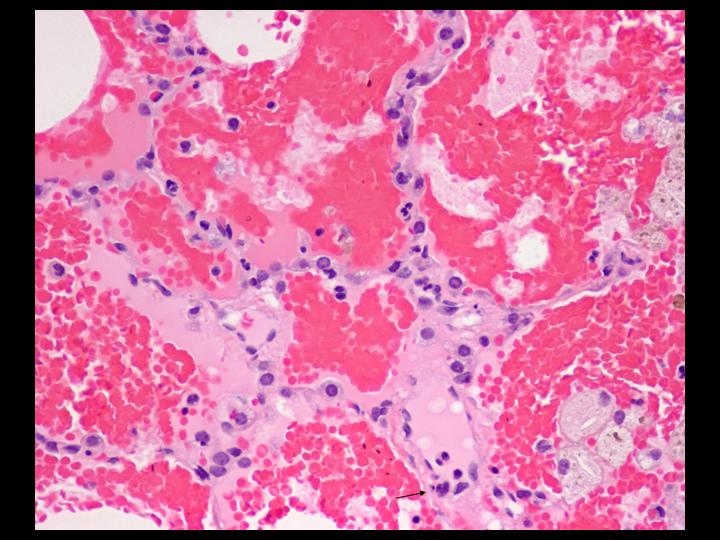

The lung biopsy was an adequate specimen comprised of a wedge of lung, 5.0 x 1.9 x 1.2 cm. The findings were jointly reviewed with the pathologists.

The next screen shows images from the lung biopsy:

| Figure 4-a | Figure 4-b | Figure 4-c |